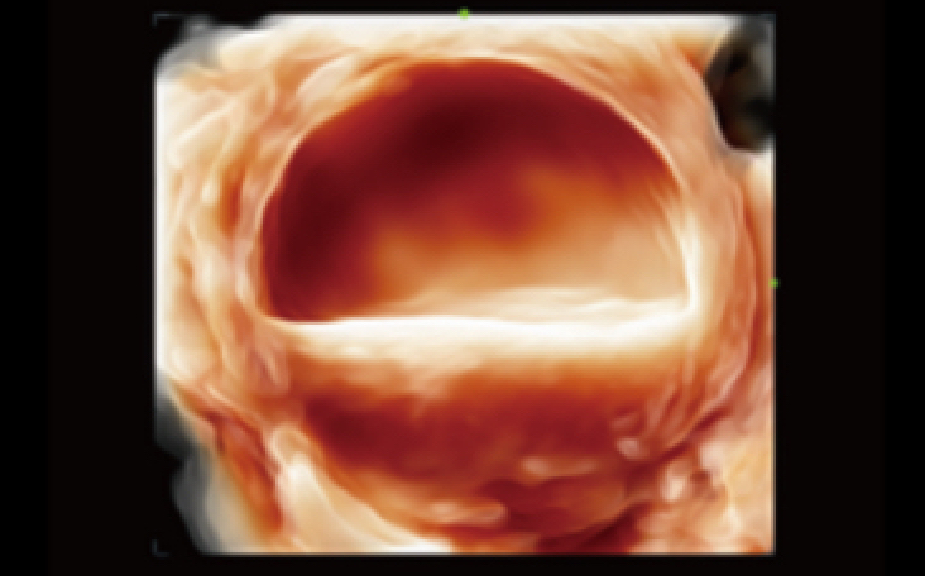

Realizing the increasing importance of ultrasound diagnosis on pelvic ?oor disorders, Smart Pelvic provides a new solution to greatly simplify the operation procedures, and to minimize the exam time for a standardized evaluation on pelvic ?oor. With extremely simple user-interaction, it generates a standard coordinate system and automatically provides all related measurements within a few seconds.